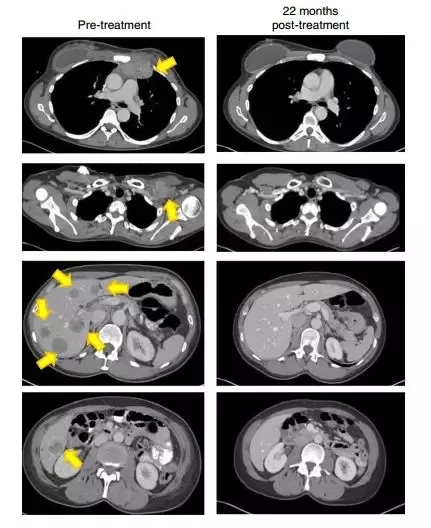

2018年,《自然醫(yī)學(xué)》(Nature Medicine)上發(fā)表的一份報(bào)告描述了在用對(duì)4種突變蛋白(SLC3A2,KIAA0368,CADPS2和CTSB)的TILs治療的患者中成功治療化學(xué)難治性激素陽(yáng)性轉(zhuǎn)移性乳腺癌。在報(bào)告發(fā)表時(shí),反應(yīng)已經(jīng)持續(xù)進(jìn)行了22個(gè)月以上,并且患者在4年后仍然沒(méi)有疾病。

22個(gè)月后,這名患者的腫瘤(黃色箭頭)消失得無(wú)影無(wú)蹤(圖片來(lái)源:《Nature Medicine》)